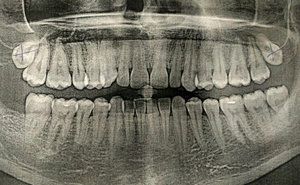

На протяжении трёх дней беспокоила несильная ноющая боль с правой стороны внизу. Сделали снимок, врач предположил, что боль возникает из-за зуба мудрости, который ещё не прорезался. И сразу записала на удаление.

Не знаю, можно ли что-то понять по приложенному снимку, но сколько примерно занимает удаление такого зуба и обязательно ли это?

Однозначно, причина беспокойств — это неправильно расположенная восьмёрка. Удаление необходимо, в противном случае мы получим скученность всего зубного ряда и потеряем седьмой зуб. Удаление сложное и требует профессионализма и опыта. Потребуется моя помощь — запишитесь к нам на приём к челюстно-лицевому хирургу.